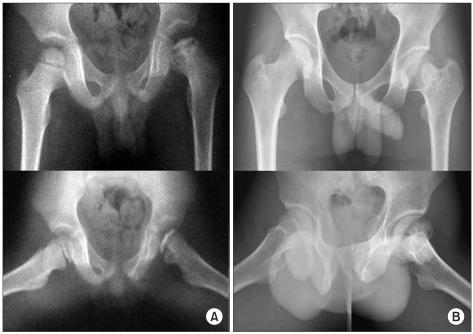

Thirty nine patients diagnosed with lateral pillar C in LCPD from May, 1977, to October, 2001 were reviewed, and their skeletal maturity was followed. The mean follow up duration was 12 years and 7 months (4 years, 6 months to 24 years, 9 months). Lateral pillar C classification was divided into C1 (50-75% collapse of the lateral pillar) and C2 (> 75%). All radiological and clinical prognostic factors were evaluated. The final results were evaluated according to the Stulberg classification.

Twenty one and 18 of the affected hips were in groups C1 and C2, respectively. According to the Stulberg classification, the final results of group C1 were better than those of C2 (p = 0.002). Patients with more head-at-risk signs had significantly poorer outcomes.

回顾 1977 年 5 月至 2001 年 10 月期间诊断为 LCPD 外侧柱 C 型的 39 例患者,并对其骨骼成熟度进行随访。平均随访时间为 12 年 7 个月(4 年 6 个月至 24 年 9 个月)。外侧柱 C 型分为 C1(外侧柱塌陷 50-75%)和 C2(>75%)。评估了所有影像学和临床预后因素。最终结果根据 Stulberg 分类进行评估。

受累髋关节中,C1 组和 C2 组分别为 21 例和 18 例。根据 Stulberg 分类,C1 组的最终结果优于 C2 组(p=0.002)。头骺受累征象较多的患者预后明显较差。